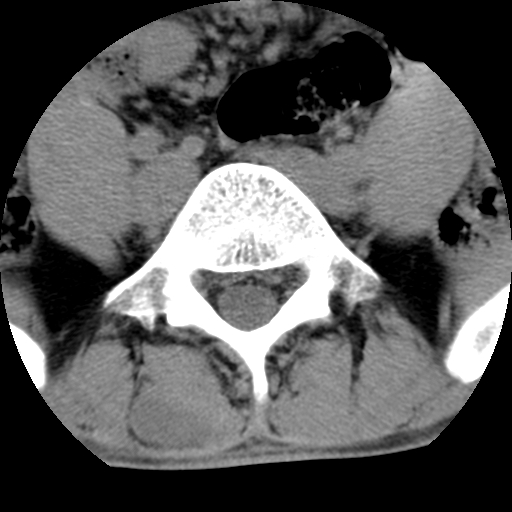

标题: CT16890:男,腰背痛.

男,腰背痛

本人诊断1tb2包虫,请会诊

1)右侧竖脊肌稍低密度肿块伴钙化(性质待定),不排除肿瘤可能;建议行进一步检查。2)腰椎间盘突出。

1.右侧竖脊肌软组织肿块伴团块状钙化,首先考虑血管瘤可能性大;建议行进一步检查;2。腰椎间盘突出。